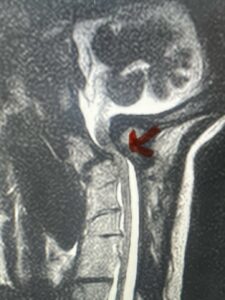

Fig. 4a: Sagittal T2-weighted cervical MRI demonstrating severe cord compression with myelomalacia of upper cervical spinal cord (red arrow). Notice the increased atlanto-dens interval (red dot).

Cervical x-rays revealed a significantly increased atlanto-axial interval (Fig. 5) On review of her imaging studies it was noted that the right C2 isthmus was very thinned by the vertebral foramen (Figs 6a, b, and c) which would make an attempt at placing a C2 pars screw dangerous. A decision was made to perform an occipital-cervical fusion because only possible unilateral fixation and an extensive C1 laminectomy to be performed eliminating a fixation point if a more traditional C1-C2 was performed. Even if C1 lateral mass screws were able to be placed one could only perform a unilateral screw construct fixation to C2. We performed an occipital cervical fusion down to C4 to get enough inferior fixation and C1 laminectomy. The decompression went well. We placed a left unilateral pars screw and bilateral C3 and C4 lateral mass screws. We placed three 12 mm screws in the midline keel (Fig. 7). Postoperatively the patient had all around improvement in her symptoms and did not qualify for rehab. Her post op films at 6 weeks (Fig. 8)